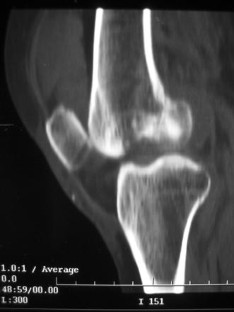

Fig. 4